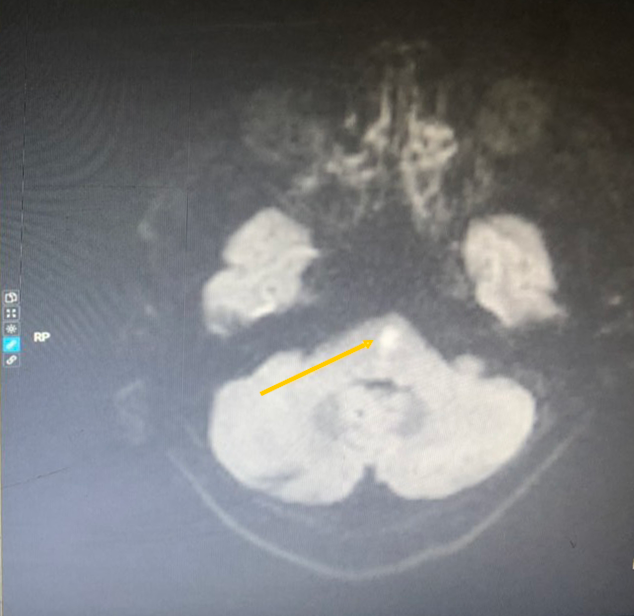

30 phút từ khi nhập viện, ông Thành nhanh chóng được cấp cứu bằng thuốc tiêu sợi huyết qua đường tĩnh mạch (rTPA). Trong cấp cứu đột quỵ cấp, tốc độ này khá nhanh theo chuẩn quốc tế (người bệnh được cấp cứu trước 45-60 phút từ khi nhập viện đến lúc được dùng thuốc tiêu sợi huyết, còn gọi là “cửa sổ cửa kim”).

Sau hai giờ dùng thuốc tiêu sợi huyết, bệnh nhân tỉnh táo, giảm nói đớ và méo miệng, tình trạng yếu nửa người phải cải thiện. Sau hai ngày điều trị, bệnh nhân có thể đi lại, ăn uống, sinh hoạt bình thường, đồng thời nhớ những chi tiết trước, trong và sau khi đột quỵ.

Vị trí nhồi máu não vùng thân não (trái) và sau khi được can thiệp tiêu sợi huyết gây đột quỵ qua hình ảnh MRI (phải). |